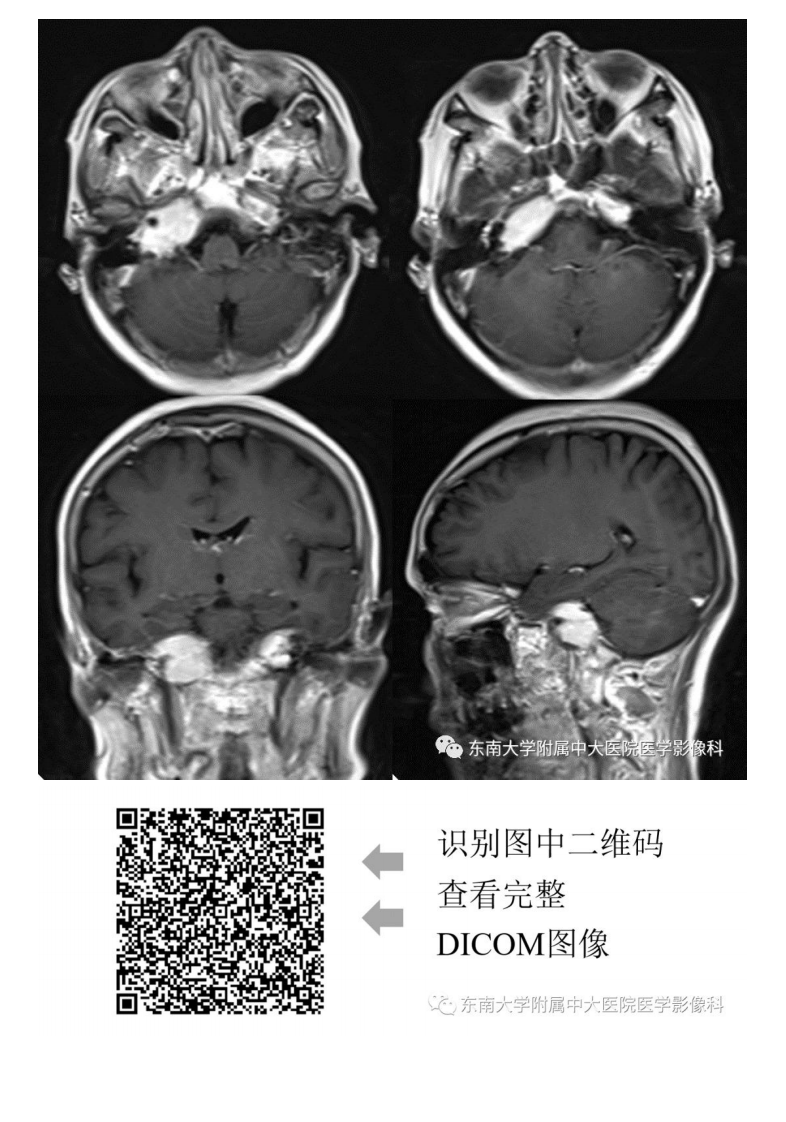

20190930_3【晨读结果公布】2019.09.29头颈部系统疾病.pdf